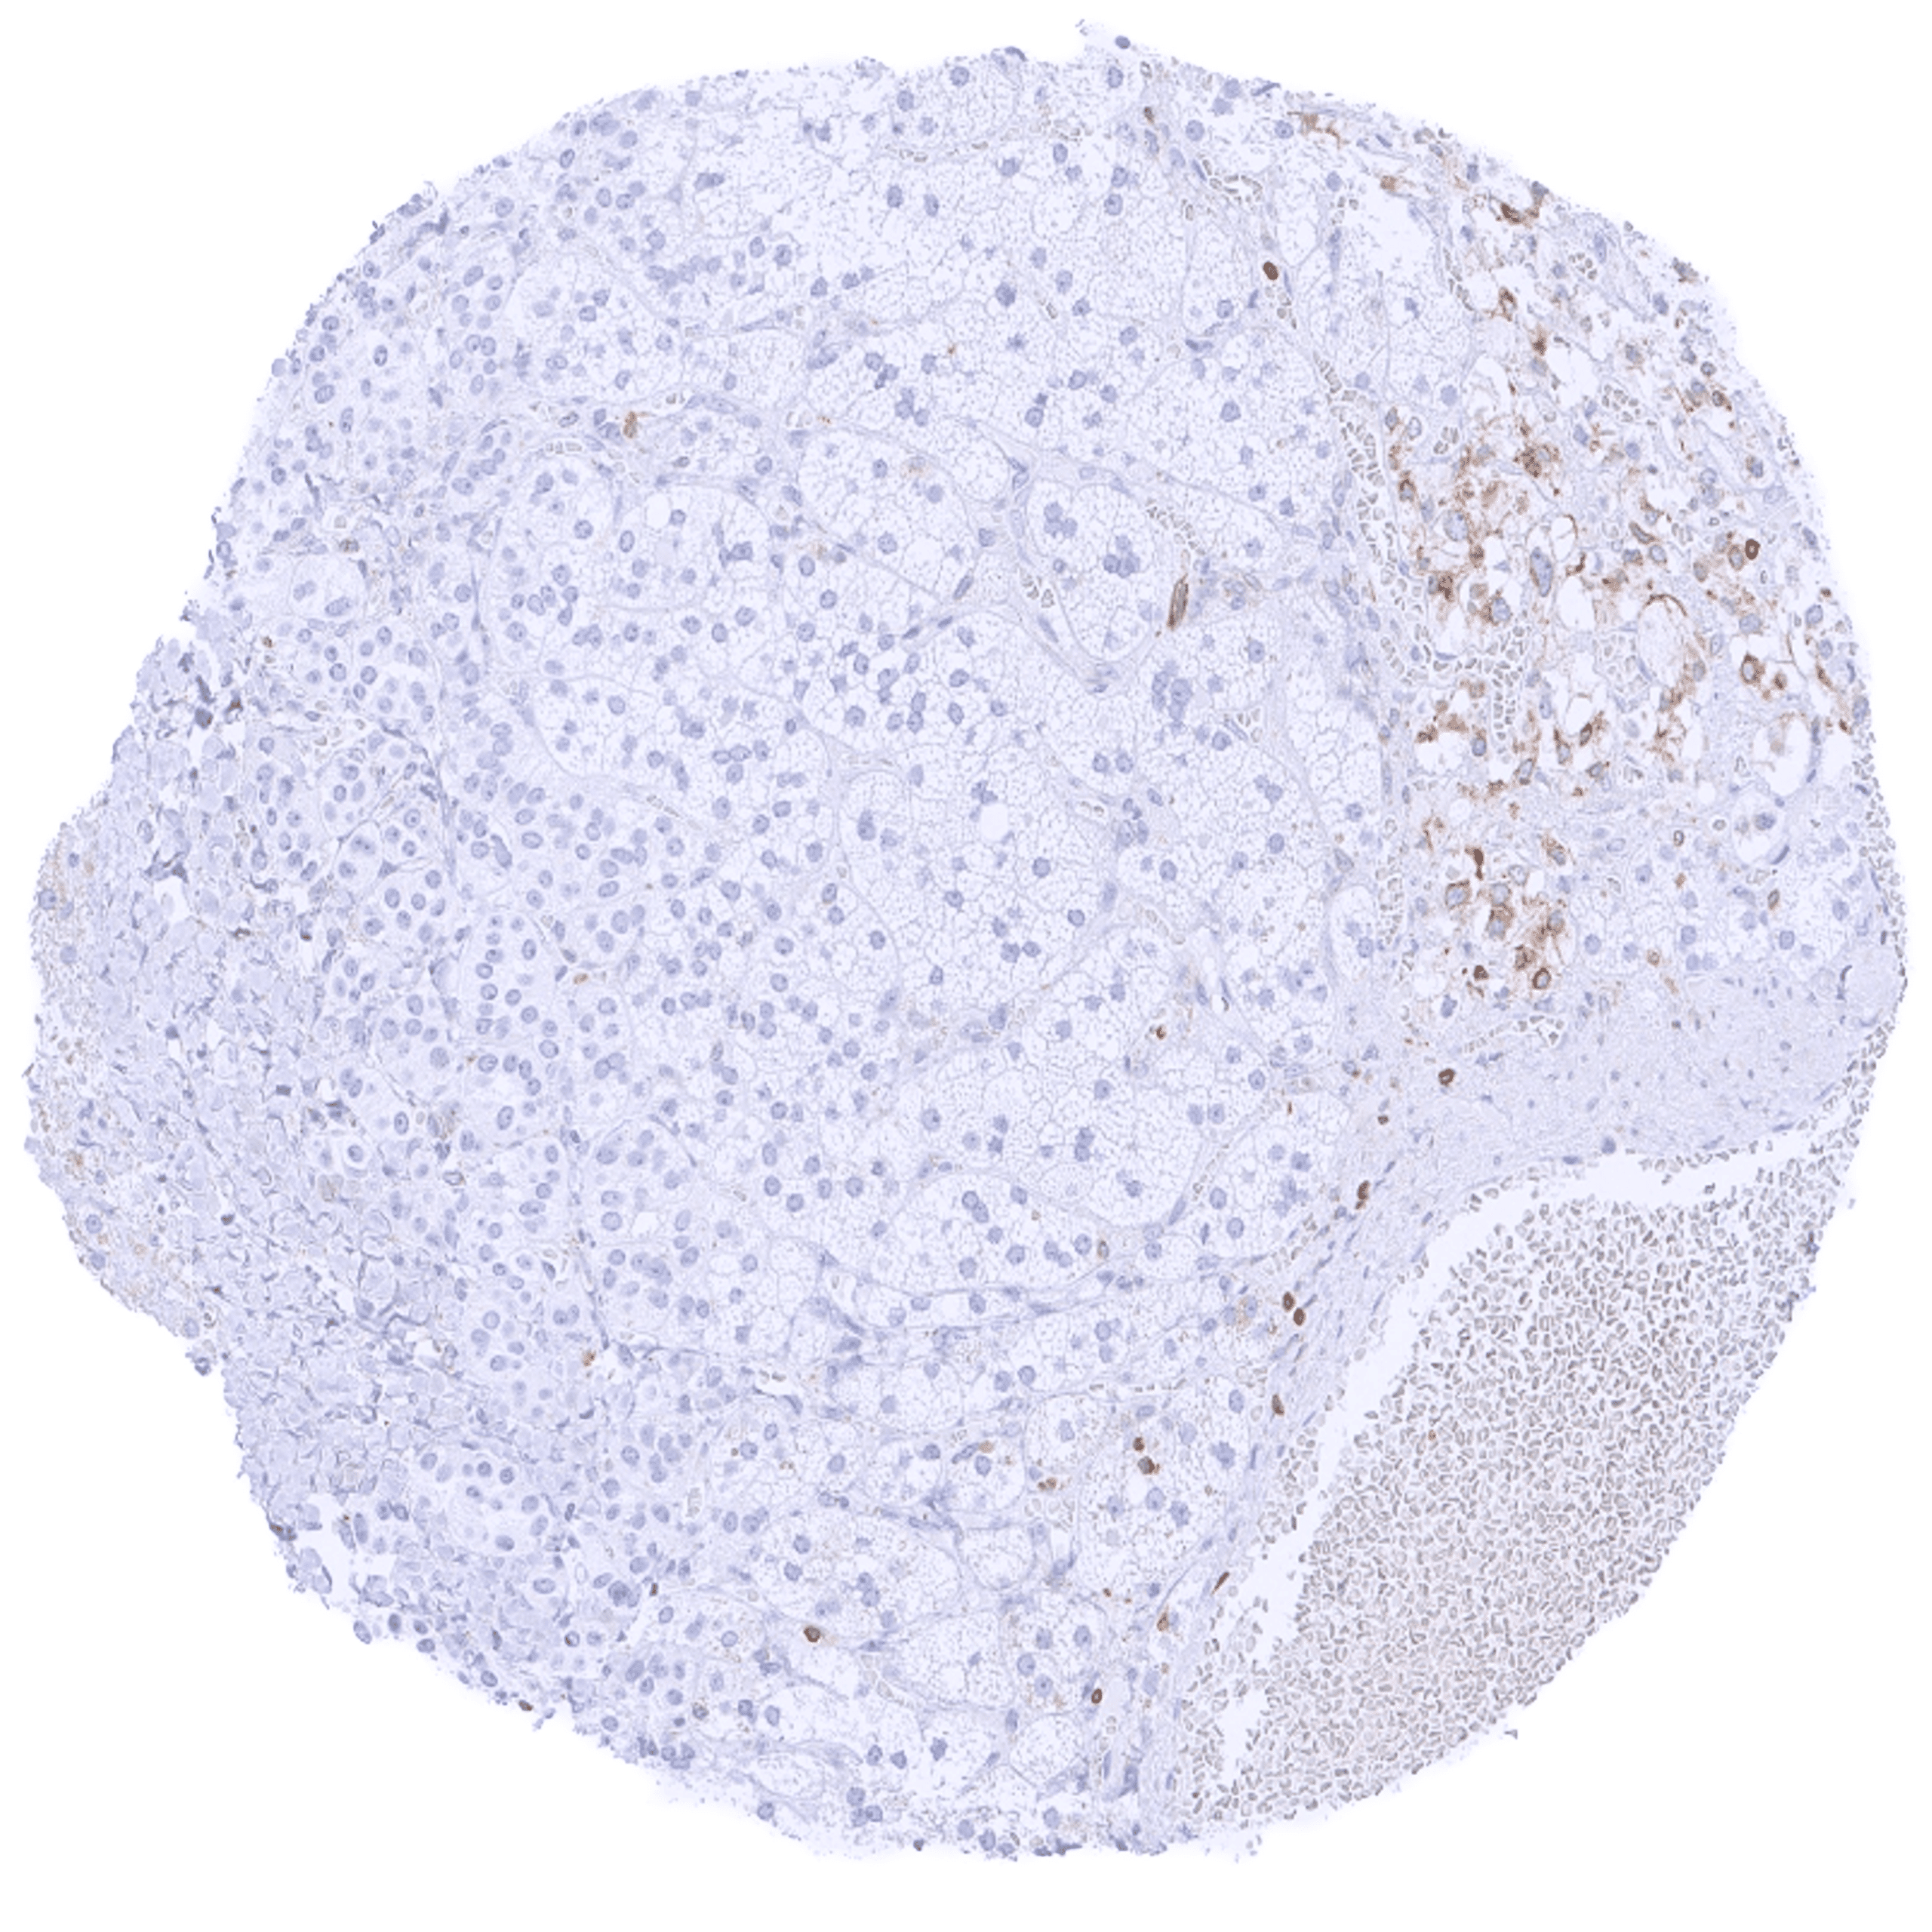

| Genitourinary | Kidney | A variable (usually weak to moderate) bcl-2 staining can occur in a fraction of (mostly distal) tubuli and collecting ducts. Staining may be more prominent in samples suffering from some degree of tissue damage. |